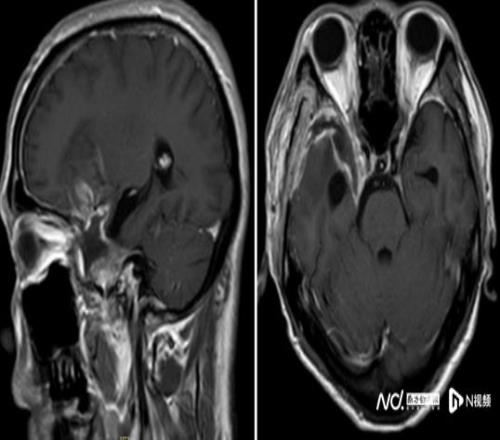

2025年10月起,他在跑步途中频繁在转弯处摔倒,偶尔还感觉一侧手脚乏力,起初并未放在心上。但随着摔跤次数不断增多,又无明显诱因地出现持续一周的头痛,他和家人终于警觉起来。同年11月中旬,陈叔家人带他在当地医院做了一次检查。MR结果如晴天霹雳:右额颞部蝶骨嵴占位病变,大小约5.5x6.6x5.8cm,考虑脑膜瘤。

鉴于肿瘤体积巨大、位置较深,考虑为右侧额颞蝶骨嵴内侧型巨大脑膜瘤,肿瘤突入垂体窝和斜坡,环绕颈内动脉及分支、视神经等重要结构,压迫脑干。手术难度是神经外科最复杂的手术之一,犹如刀尖上行走,且已出现进行性神经功能缺损症状:肢体乏力,视力受损,视物重影等,病情复杂、手术风险极高。

经过近8个小时的精细操作,肿瘤被完整切除,重要神经血管结构完好保留。术后患者恢复良好,顺利出院,经过积极康复后,陈叔有望重回马拉松赛场。